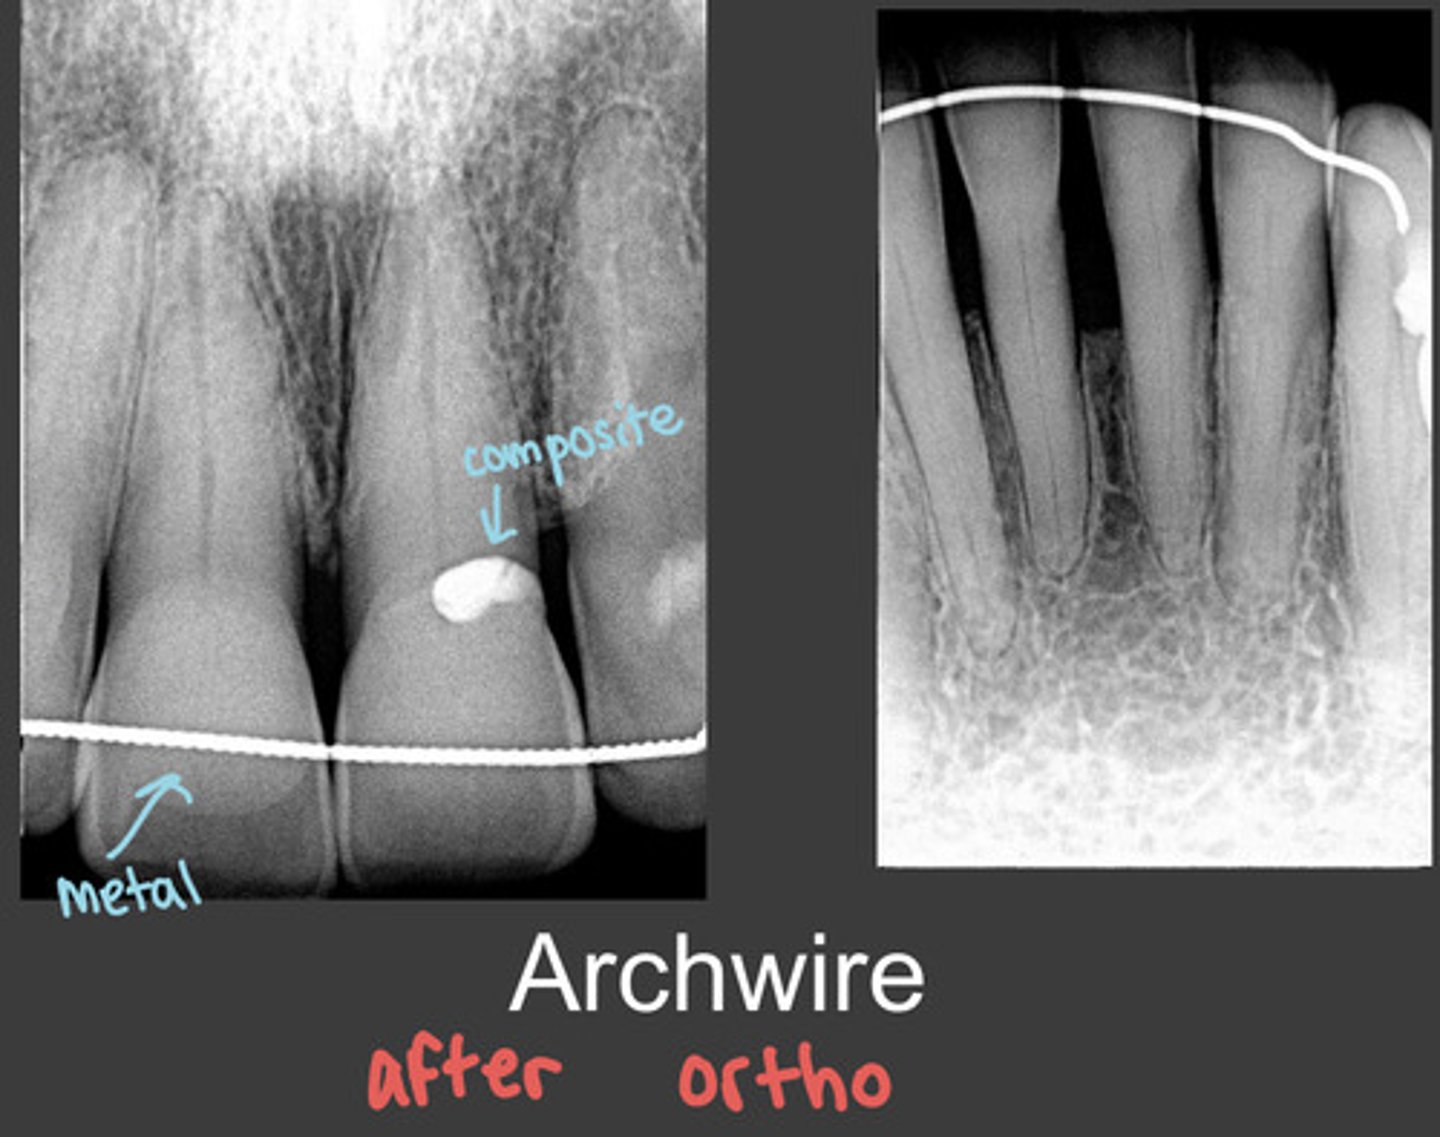

archwire